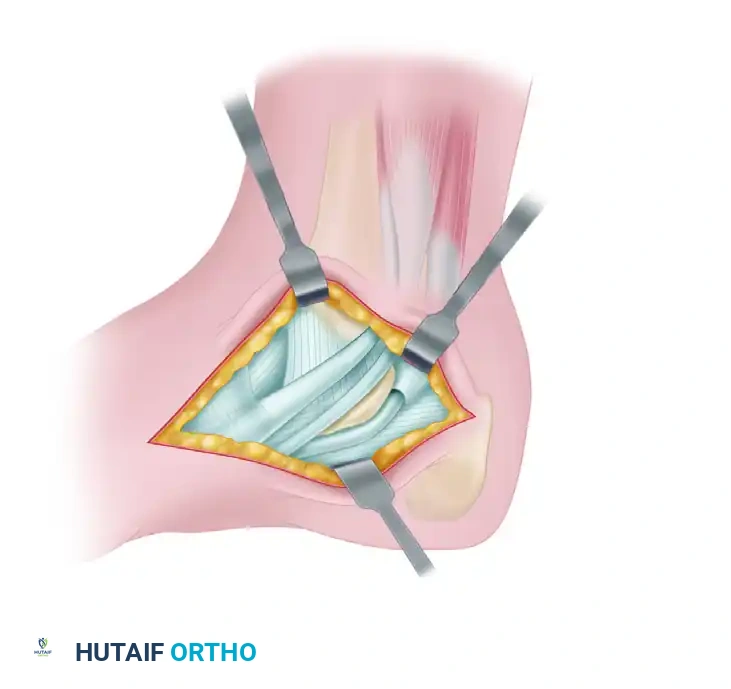

5. Resection of the Coalition

- With all four margins (proximal, distal, dorsal, plantar) clearly exposed, begin the resection.

- Utilize a 1/4-inch to 1/2-inch straight osteotome to outline and determine the margins of the resection. Remove the bulk of the bridging bone.

- Transition to a 3- to 4-mm high-speed burr for the final, precise resection. Continue burring until healthy, glistening hyaline cartilage is visible on both the talar and calcaneal surfaces of the middle facet.

FIGURE 82-85 B: The coalition is systematically removed with an osteotome and burr until the resection is flush with the posterior facet and normal cartilage is visualized.

🚨 Surgical Warning: The Most Common Error

The most frequent cause of failure and recurrence is inadequate resection. The surgeon must extend the resection sufficiently distally and proximally to view normal cartilage on both sides of the joint. Cartilage must be seen throughout the entire depth of the resected area, leaving absolutely no areas of fibrous or bony connection.

- Intraoperative Assessment: Once resection is complete, apply subtalar stress (inversion and eversion). The surgeon should immediately observe and palpate restored motion at the subtalar joint.